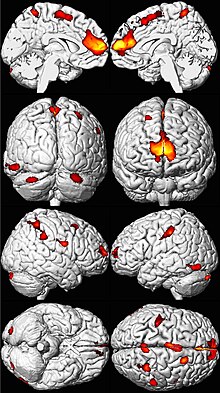

.png)

Lead poisoning can cause a variety of symptoms and signs which vary depending on the individual and the duration of lead exposure.[11][12] Symptoms are nonspecific and may be subtle, and someone with elevated lead levels may have no symptoms.[13] Symptoms usually develop over weeks to months as lead builds up in the body during a chronic exposure, but acute symptoms from brief, intense exposures also occur.[14] Symptoms from exposure to organic lead, which is probably more toxic than inorganic lead due to its lipid solubility, occur rapidly.[15] Poisoning by organic lead compounds has symptoms predominantly in the central nervous system, such as insomnia, delirium, cognitive deficits, tremor, hallucinations, and convulsions.[16]